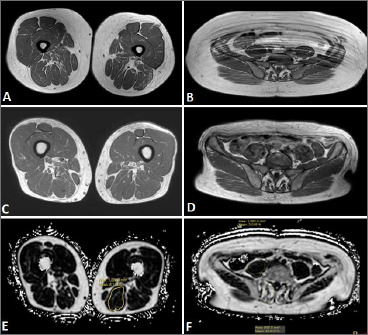

Objective: This case study aimed to evaluate the safety and efficacy of sleeve gastrectomy surgery in an obese patient with Late-onset Pompe disease (LOPD) and to explore the potential role of bariatric surgery in improving clinical outcomes and promoting a more physiological body composition when dietary and physical interventions fail.

Methods: We describe a case of an obese LOPD patient who underwent sleeve gastrectomy, with clinical follow-up conducted to monitor motor and respiratory functions, as well as patient-reported outcome measures (PROMs), over time.

Results: The surgery was well-tolerated without significant complications, and prolonged stability in motor and respiratory functions was observed. Furthermore, the patient reported improvements in quality of life and PROMs following weight loss.

Conclusion: This case suggests that bariatric surgery, specifically sleeve gastrectomy, may be a safe and effective complementary strategy for weight loss in LOPD patients, offering benefits in functional stability, and quality of life.